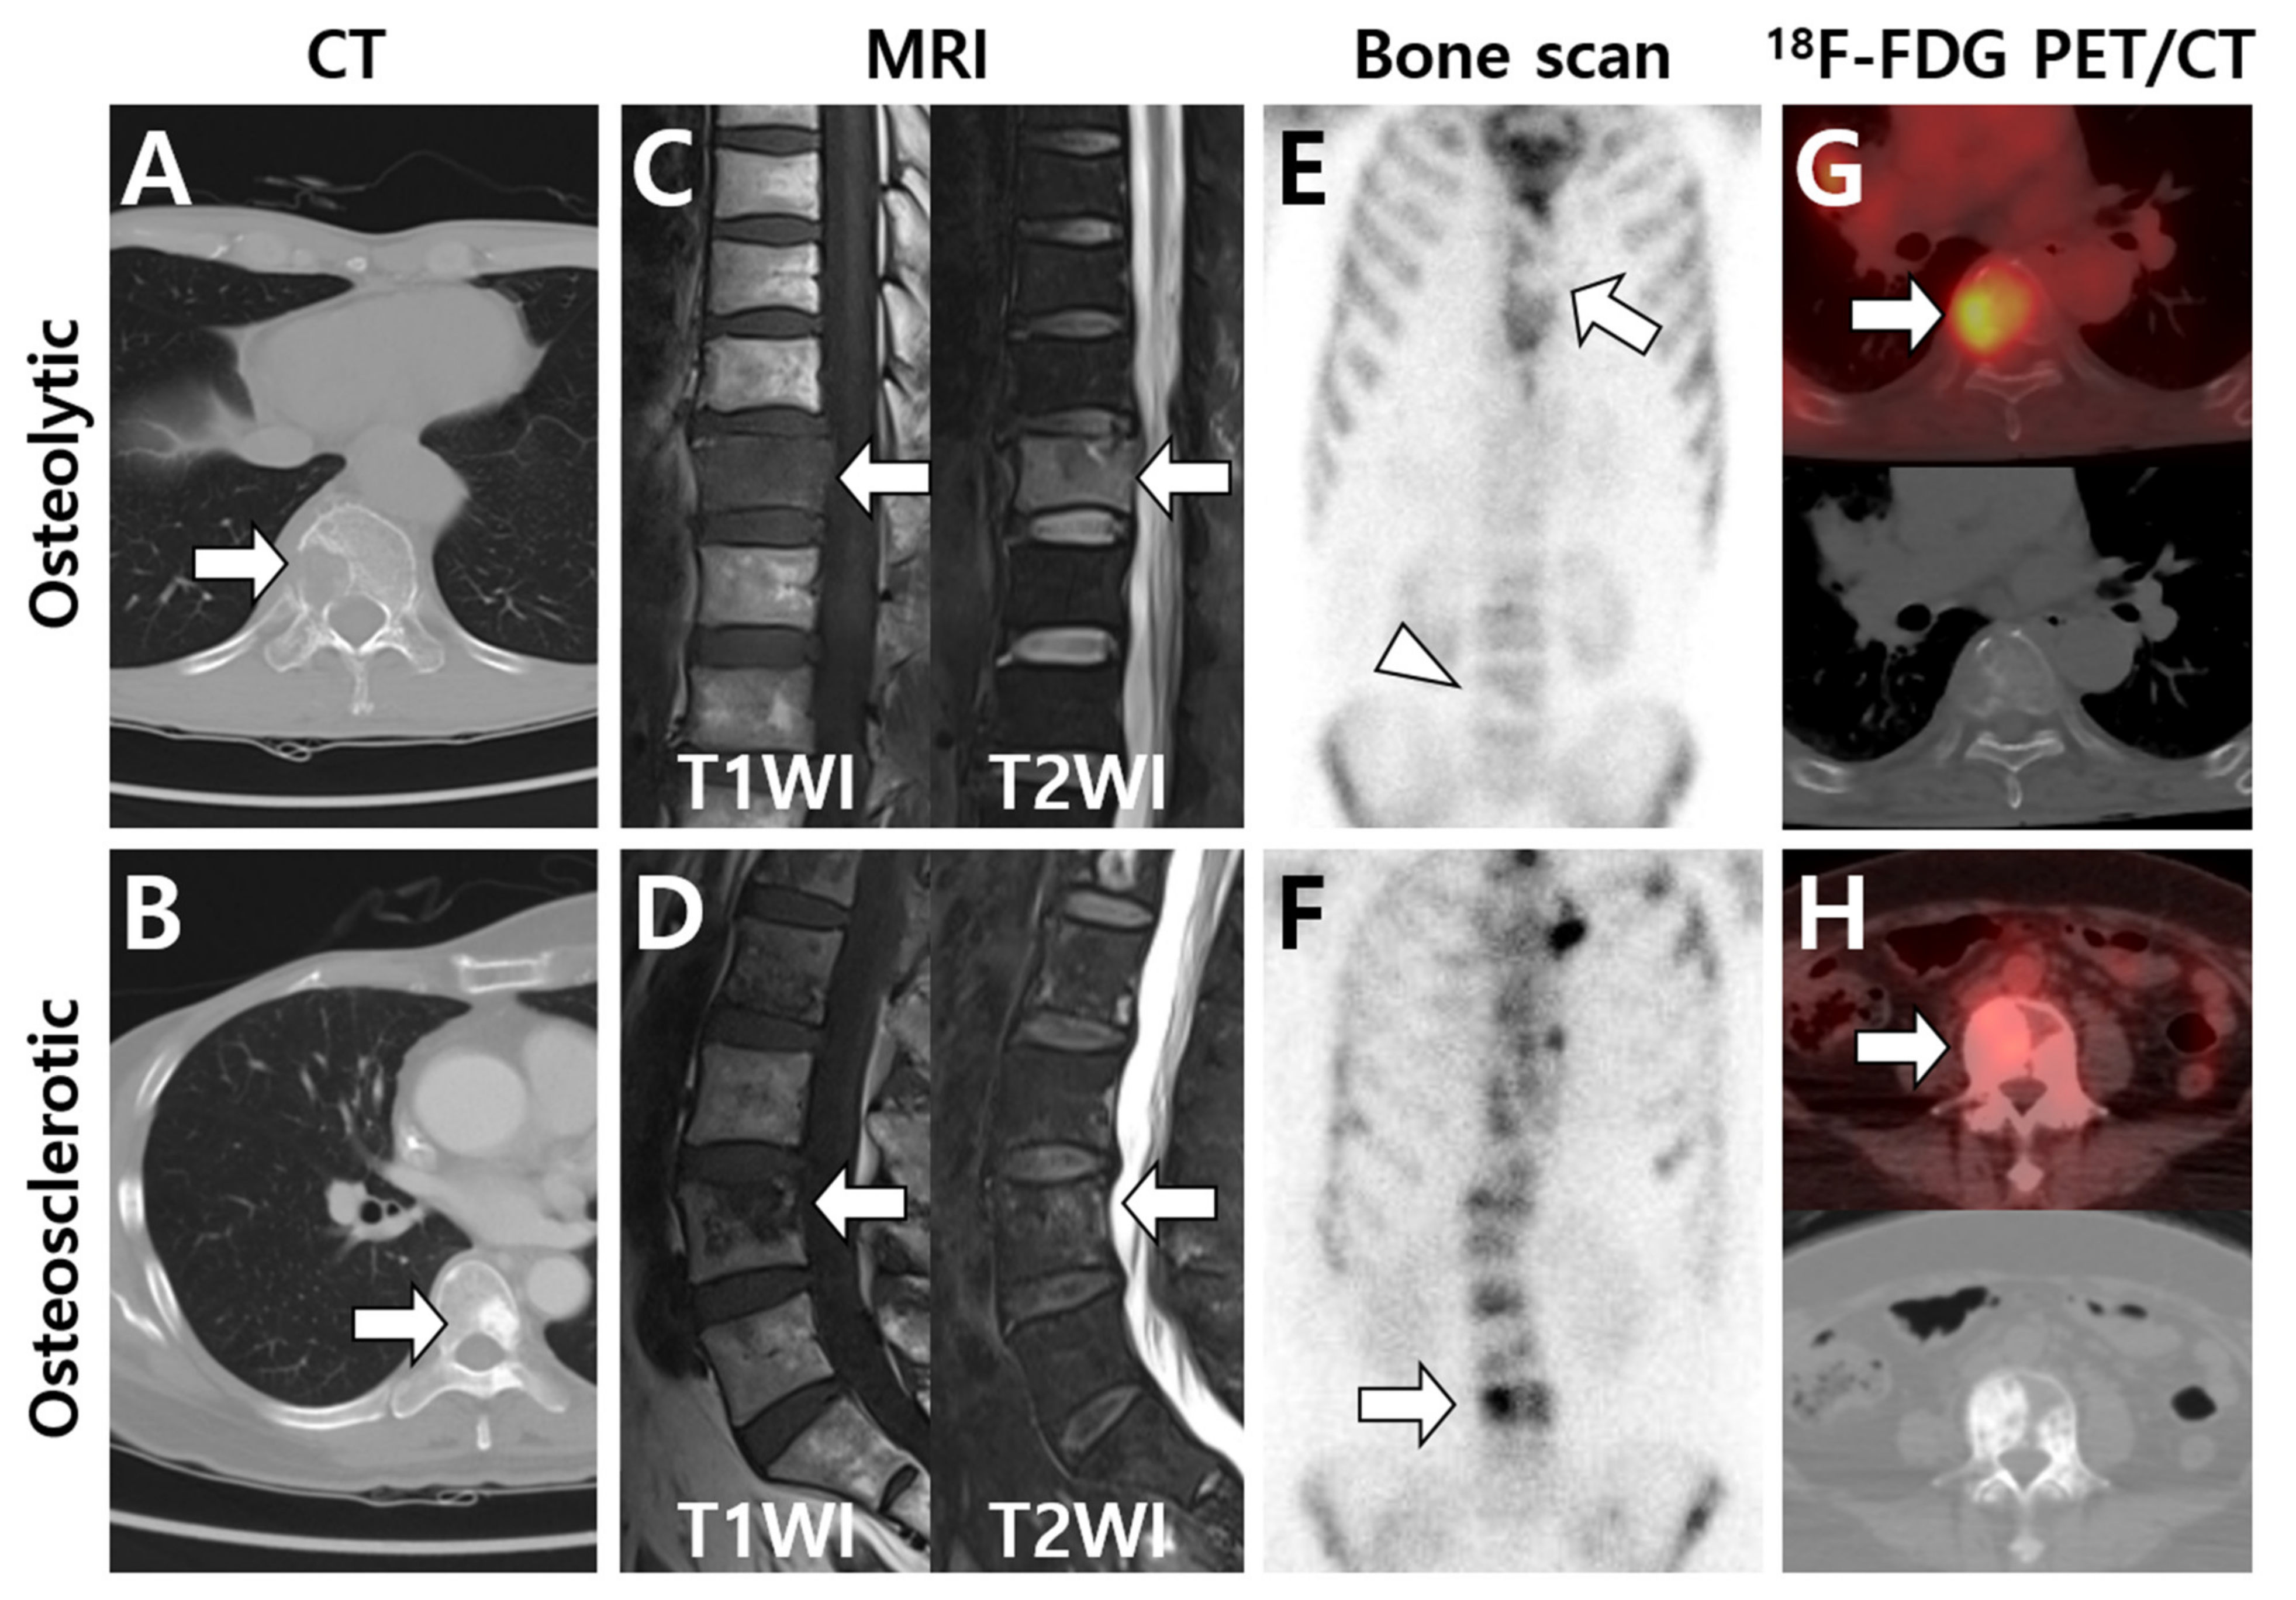

3.1. Multimodal Imaging According to the Primary Tumor Site and Histologic Type

3.2. Multimodal Imaging According to the Differentiation Status of the Primary Tumor